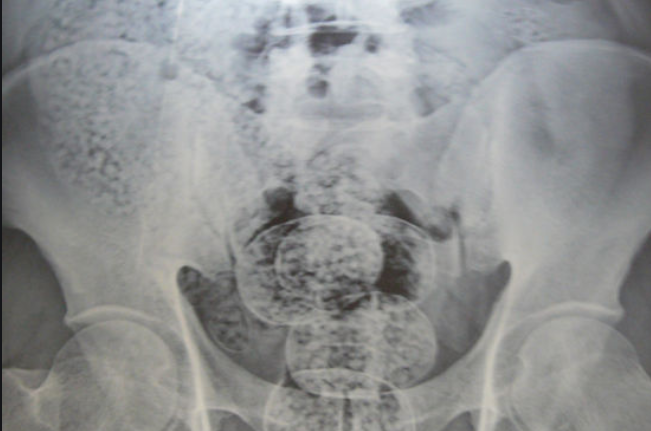

2013年2月底,被告人袁某邀约被告人臧某帮其男友林某运输毒品。同年3月1日,袁某与臧某在M国X市一旅馆内将8坨毒品甲基苯丙胺片剂藏于体内。其中,袁某藏匿5坨,臧某藏匿3坨,排出毒品交给他人。臧某从袁某处获得6000元报酬。

2013年3月,袁某邀约臧某,二人又邀约被告人周某帮林某运输毒品甲基苯丙胺片剂到C市。3月15日,林某将毒品甲基苯丙胺片剂送至臧某、周某在M国X市暂住的旅馆,臧某、周某分别将4包、3包甲基苯丙胺片剂藏于体内。二人乘坐袁某联系的摩托车从M国到Y省,在某机场乘飞机前往C市。次日凌晨1时许,臧某,周某在C市机场被抓获归案。民警分别从臧某、周某处查获从体内排出的毒品甲基苯丙胺片剂183.9克、139.4克。经鉴定,上述查获的甲基苯丙胺片剂中均检出甲基苯丙胺和咖啡因成分。其中,从臧某处查获的甲基苯丙胺片剂的甲基苯丙胺含量为9.7%,从周某处查获的甲基苯丙胺片剂的甲基苯丙胺含量为10.2%。6月8日,袁某被抓获归案。